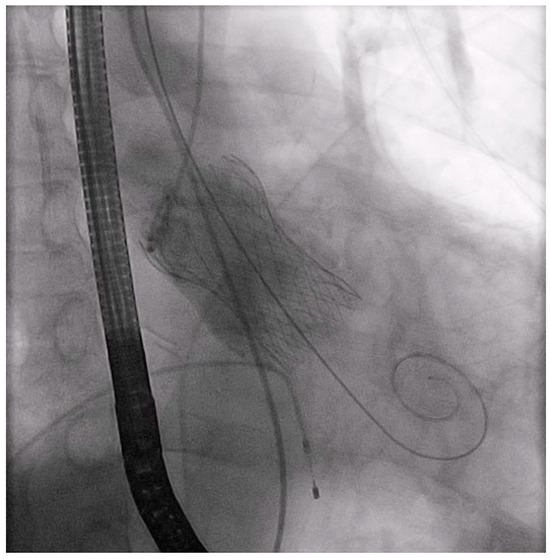

Trans-Brachial TAVI in a Patient with Aortic Isthmus Stenosis: A Case Report

2. Materials and Methods: Case Presentation